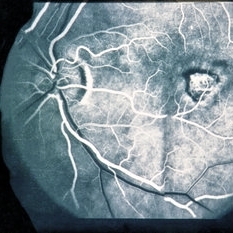

FA After Thermal Laser for CNVM

Feb 19 2015 by H. Michael Lambert, MD

AV phase of fluorescein angiogram with RPE window defect after thermal laser.

Condition/keywords: choroidal neovascular membrane (CNVM), laser, window defect